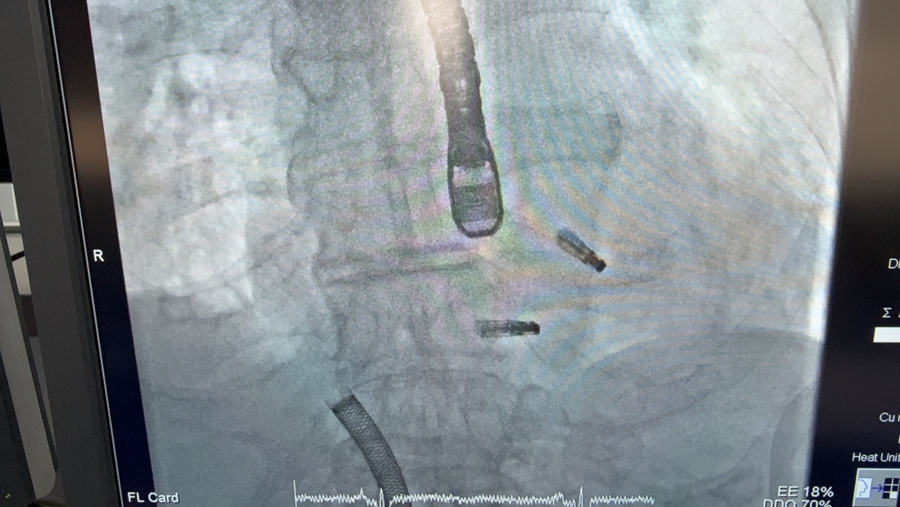

图中可见二三尖瓣各植入一枚夹子,上方为食说念超声探头,下方为运输鞘

手术由何奔说明主刀,他通过股静脉穿刺,经房拆开穿刺置入大鞘,送入夹子,调弯到位,开夹调相,下潜捕捞一气呵成,仅用20多分钟便告捷夹住二尖瓣腱索断裂处。心超声久了:二尖瓣反流从重度片刻降至轻细量。阐述安全后,武断开释夹子。随后,大鞘被撤离到右心房,转移标的,瞄准三尖瓣最大反流处送入一枚更大的夹子,精确夹合。三尖瓣反流从重荷度飞快降至轻度。